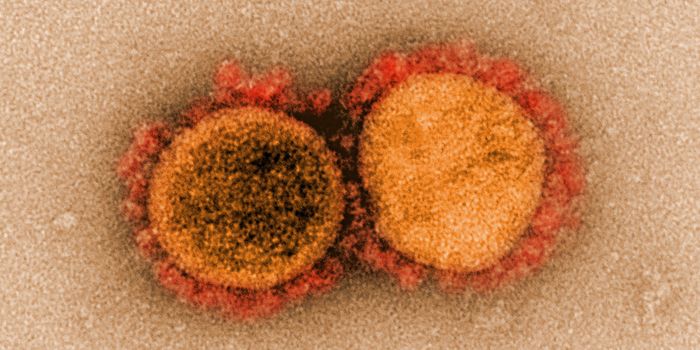

MAY 03, 2020Genetics & GenomicsThe origin of SARS-CoV-2, the pandemic virus that causes COVID-19, has become politicized as leaders seek to place blame ...

JUL 06, 2020MicrobiologyThe pandemic coronavirus has caused a wide range of different symptoms, and as time goes on, we may find that it can hav ...

JUL 05, 2020Cell & Molecular BiologyThe pandemic virus SARS-CoV-2 enters the body through the respiratory system to cause the illness COVID-19. But we know ...

JUN 29, 2020MicrobiologyVaccines that contain live attenuated viruses may be giving people some protection from serious cases of COVID-19 that i ...

FEB 22, 2021MicrobiologyReporting in Science, researchers have created an antiviral nasal spray that could help us get the COVID-19 pandemic und ...

SEP 01, 2021MicrobiologyIt's been generally assumed that people who get infected with SARS-COV-2 will develop antibodies to the virus, which cau ...

MAR 18, 2020MicrobiologySARS-CoV-2 is a coronavirus that causes an illness called COVID-19. There are now well over 210,000 confirmed cases worl ...